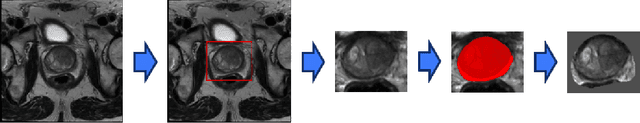

Abstract:Magnetic Resonance Imaging (MRI) plays an important role in identifying clinically significant prostate cancer (csPCa), yet automated methods face challenges such as data imbalance, variable tumor sizes, and a lack of annotated data. This study introduces Anomaly-Driven U-Net (adU-Net), which incorporates anomaly maps derived from biparametric MRI sequences into a deep learning-based segmentation framework to improve csPCa identification. We conduct a comparative analysis of anomaly detection methods and evaluate the integration of anomaly maps into the segmentation pipeline. Anomaly maps, generated using Fixed-Point GAN reconstruction, highlight deviations from normal prostate tissue, guiding the segmentation model to potential cancerous regions. We compare the performance by using the average score, computed as the mean of the AUROC and Average Precision (AP). On the external test set, adU-Net achieves the best average score of 0.618, outperforming the baseline nnU-Net model (0.605). The results demonstrate that incorporating anomaly detection into segmentation improves generalization and performance, particularly with ADC-based anomaly maps, offering a promising direction for automated csPCa identification.